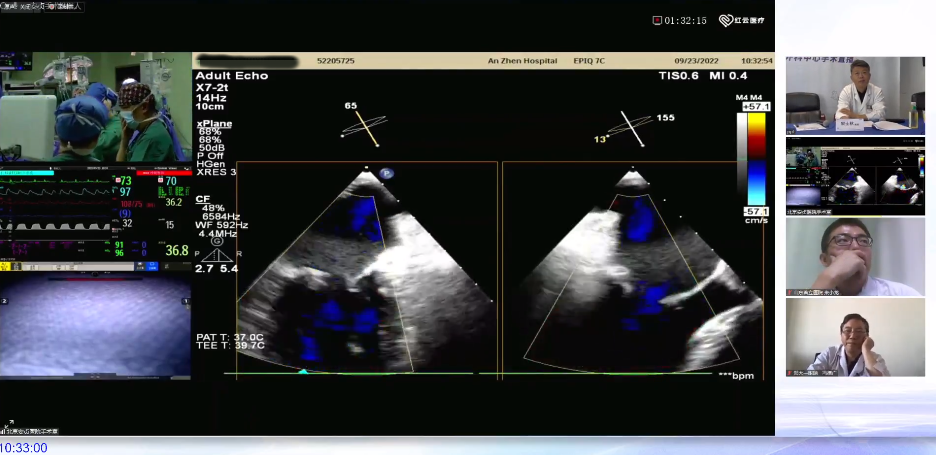

2022年9月23日,尤斌教授担任主席召开的“心动在线-微创心脏外科中心手术直播——机器人二尖瓣修复手术”活动圆满结束。

在会议上,尤斌教授演示了一例机器人二尖瓣修复+三尖瓣修复+房颤射频消融手术,手术过程流畅,手术效果良好,获得了线上观众的一致赞叹。尤斌教授特别强调,机器人在二尖瓣修复手术中有着明显的优势,大家应该积极了解学习。